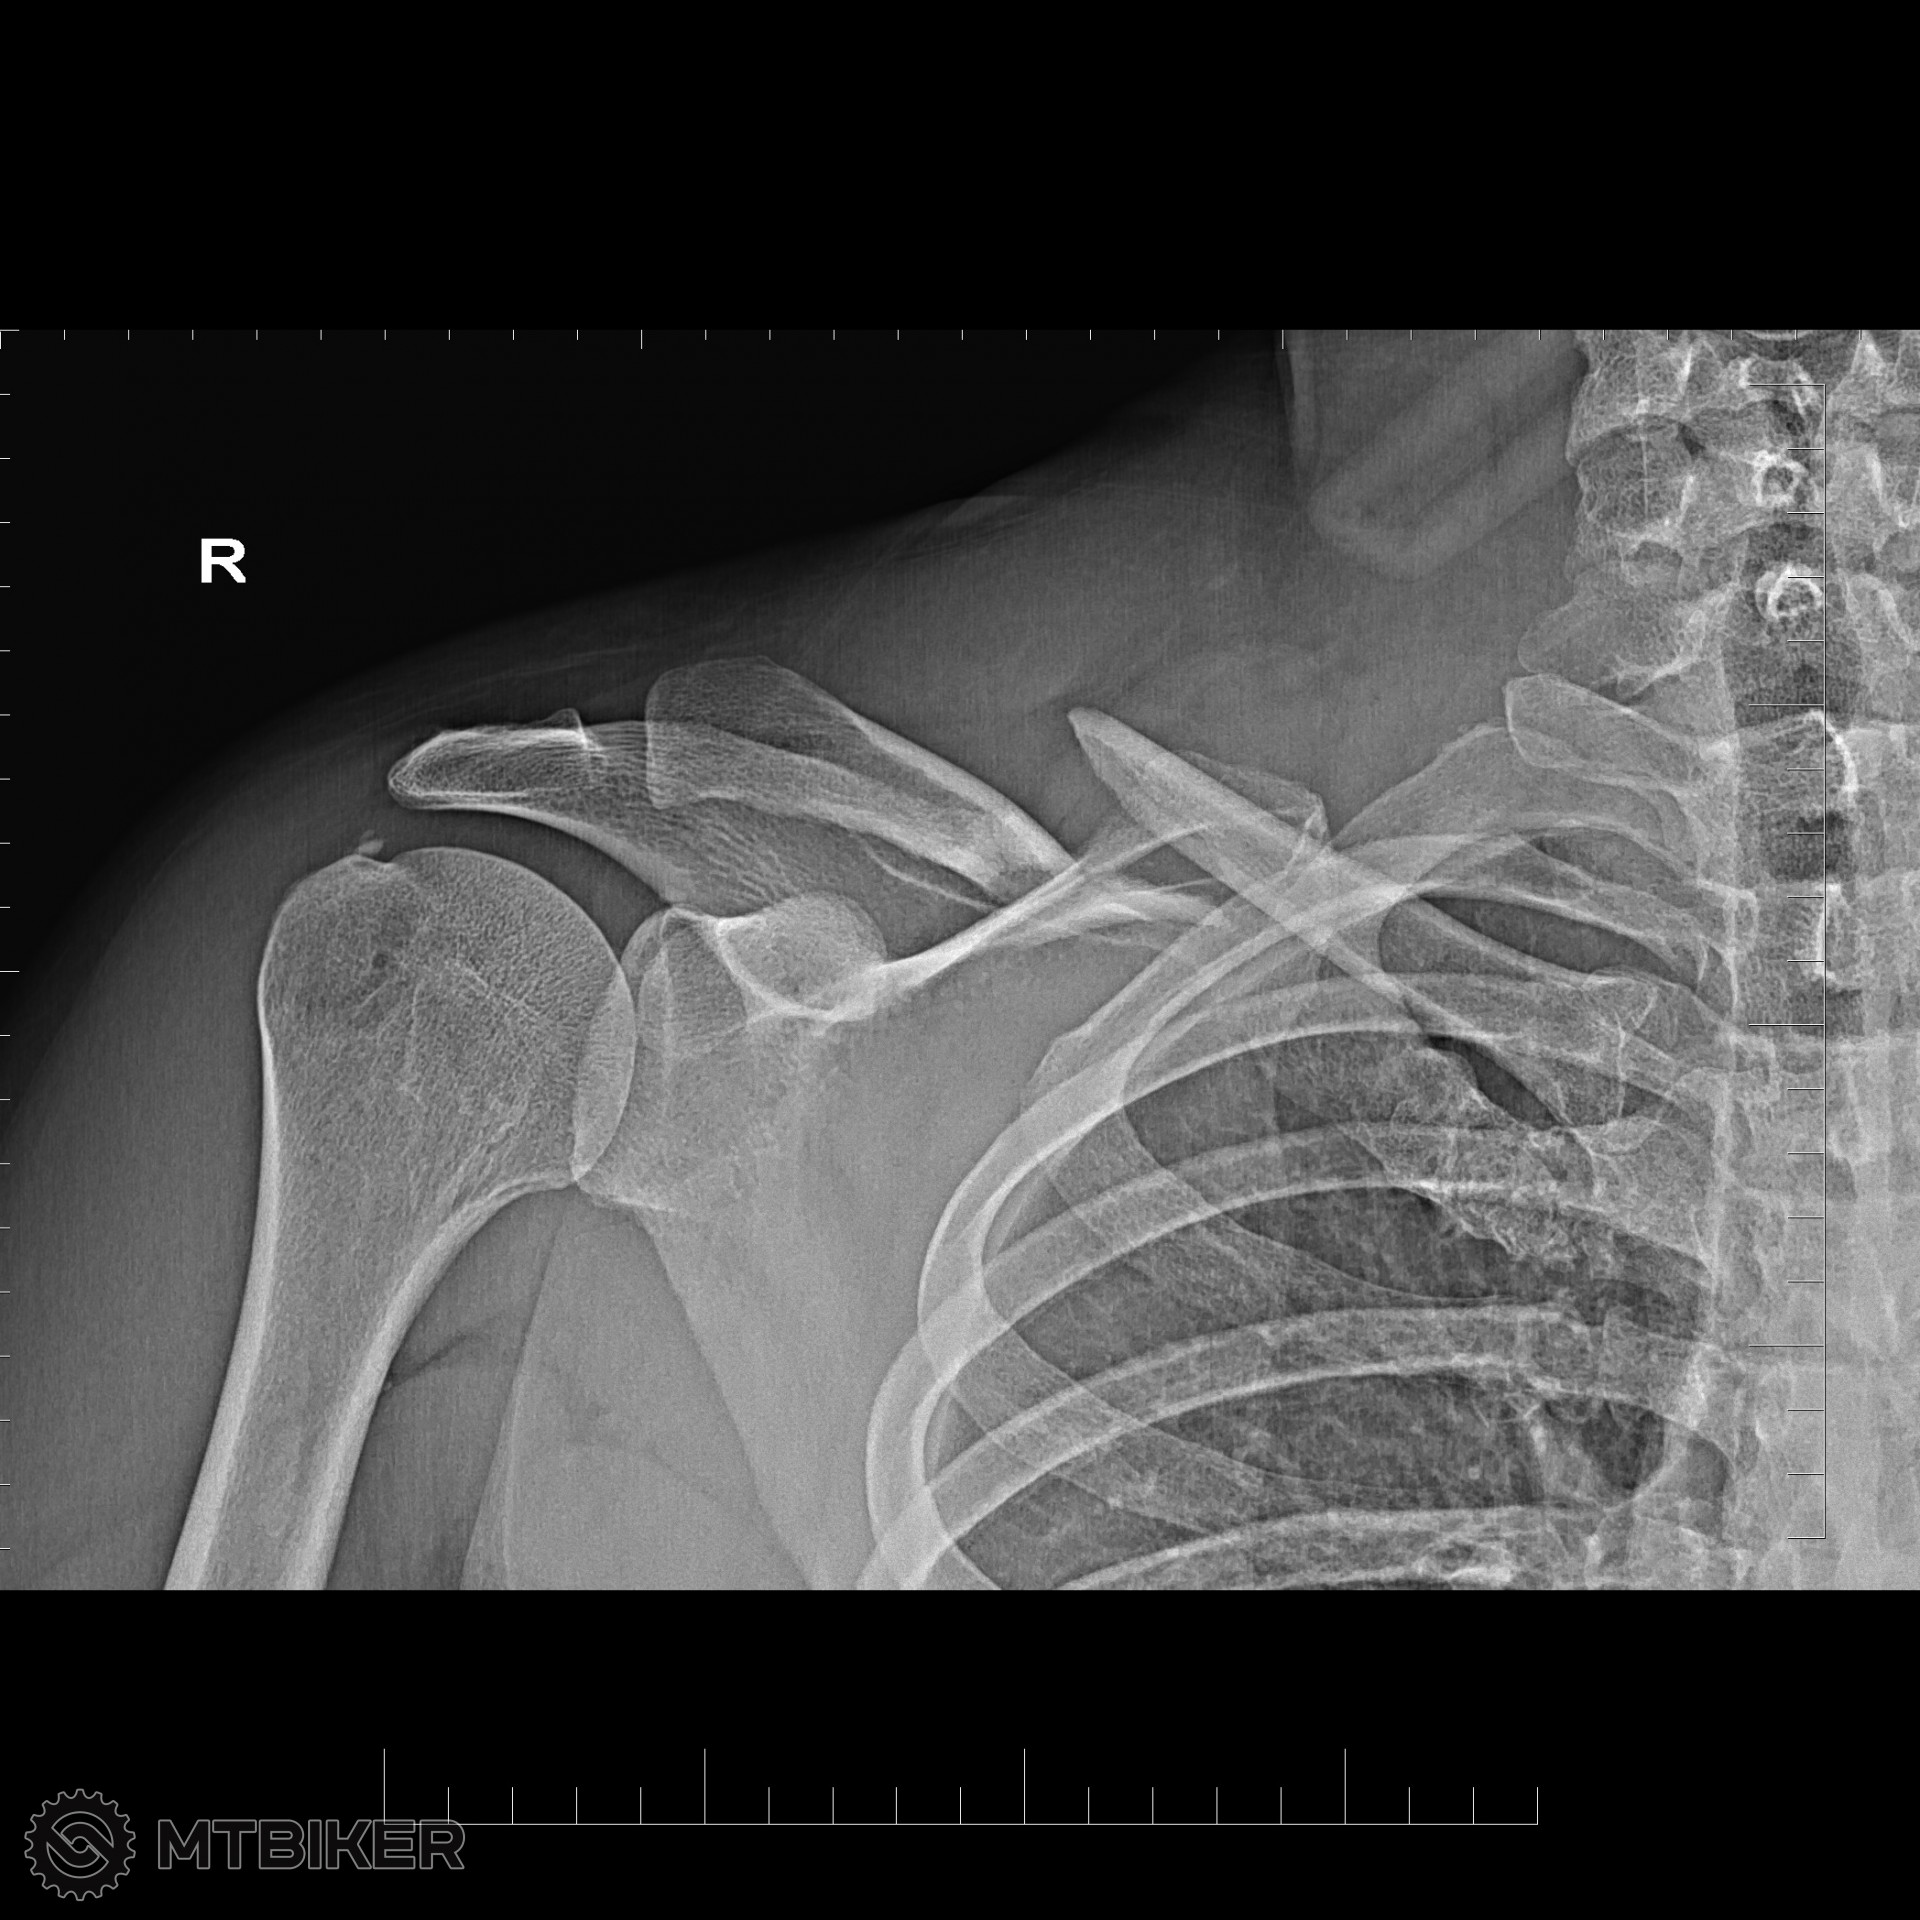

Takto som dopadol pri testovacom dni Orbea v Hradku... esteze som nemal kameru...